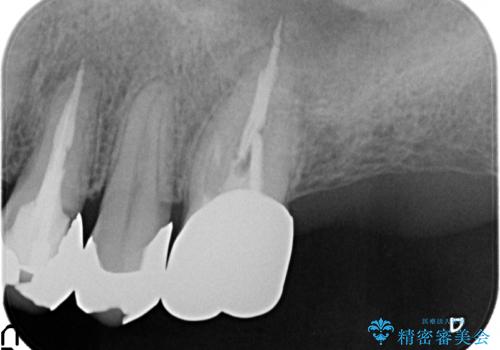

PGA(ゴールド)クラウン 脱離した銀歯の治療

- 古い銀歯が外れたので診て欲しいといらっしゃった方の症例です。

再根管治療後、PGA(ゴールド)クラウンによる補綴を行いました。

- PGA(ゴールド)クラウン…¥80,000、仮歯…¥10,000、ファイバーコア…¥20,000費用は治療当時の料金となります